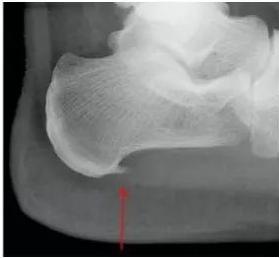

图1.跟骨骨刺(图片来源于网络)

此结构最薄弱的部分就是"弓弦"与"弓体"相交接的地方,也就是足跟处,正是临床上最常见的骨刺发生部位。这个地方反复受到刺激和损伤,导致了在应力方向骨刺的形成。所以我们仔细观察X光片会发现,骨刺方向是水平而不是垂直向下的。通过骨质增生的方式,增加韧带与骨骼的接触面积,减少骨骼单位面积上的受力,使得接触面更加稳定,重新变得平衡。